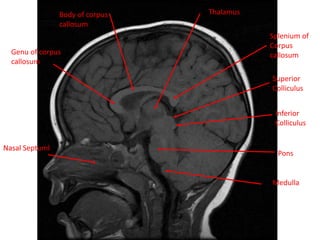

NasalNasal Septuml

Medulla

Body of corpus

callosum

Pons

Superior

Colliculus

Inferior